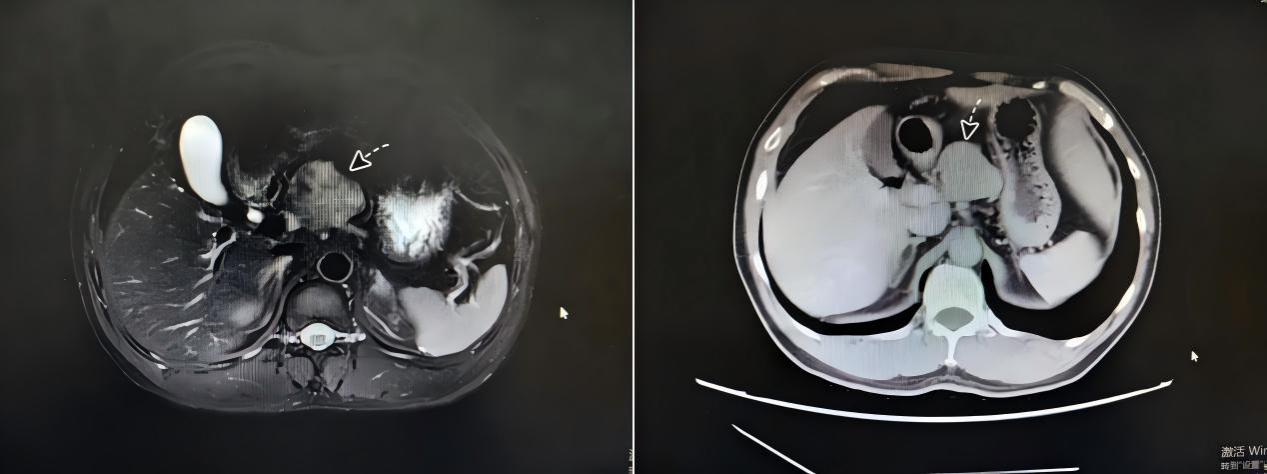

患者有着20多年乙肝病史,在一次复查中意外发现肝脏存在占位性病变。进一步检查确认,肿瘤位于肝脏深处的尾状叶。这一区域解剖结构复杂、空间狭小,且被肝脏主要血管系统紧密包绕,手术视野暴露极差,被视为“肝脏外科最后的禁区”。面对病情,患者及家属焦虑万分:如果选择传统开腹手术,创伤大、恢复难;而若放任不管,肿瘤随时可能恶化,危及生命。

面对这一棘手病例,南华医院肝胆外科李卫主任医师及团队经过详尽的术前评估与讨论,决定采用先进的腹腔镜微创技术为患者解除病痛。李卫介绍:“传统开腹手术对于这类患者来说,无异于一场‘浩劫’。而腹腔镜技术就像把医生的‘眼睛’和‘器械’通过钥匙孔般的通道送入体内,在高清放大的视野下,我们可以清晰地分辨血管和肿瘤的边界,实现毫米级的精细操作。”相较于传统手术,腹腔镜肝尾状叶切除术具有创伤小、出血少、恢复快、并发症少等显著优势。

手术过程中,李卫带领团队在狭小的空间内灵活操作,如同绣花般精细地游离、钳夹、凝闭、离断血管,成功将肿瘤从紧贴的下腔静脉旁完整剥离,整个过程出血量极少,未输血,手术圆满成功。这一高难度手术的完成,不仅体现了团队深厚的解剖学知识积累和成熟的腹腔镜操作技巧,更彰显了南华医院肝胆外科在处理复杂、疑难肝脏疾病方面的强大能力。